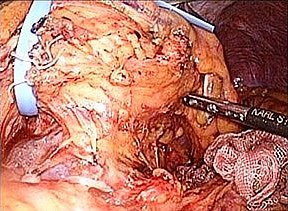

腹腔鏡下(補助下)膵体尾部切除術の実際

従来の開腹手術では15cm以上の皮膚切開が必要で、美容面(整容性)や術後の痛みなど

が問題でした。一方、腹腔鏡手術では、4cmの小切開と5〜10mmの3〜4ヶ所の傷で

手術が可能です(図)。専用の器械を用いて膵切離を行い、小切開創から体外に取り出

します。術後の傷は小さく美容面で優れており、また術後の痛みも軽減されます。また

症例によっては完全腹腔鏡下膵体尾部切除を行う場合もあります。